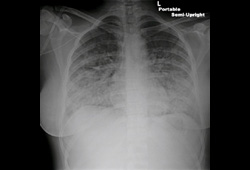

- radiografía de tórax